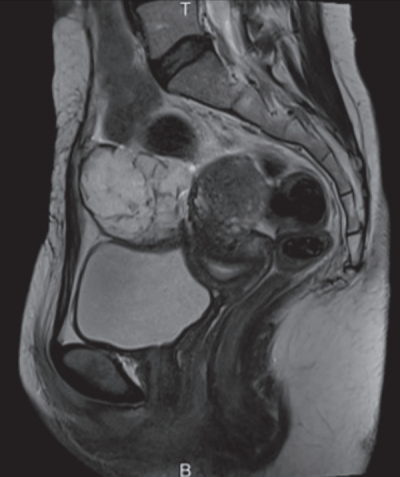

尿所見:蛋白(-)、糖(-)、潜血(-)。血液所見:赤血球 480 万、Hb 13.9 g/dL、Ht 41 %、白血球 4,400、血小板 24 万。血液生化学所見:総蛋白 6.8 g/dL、アルブミン 4.2 g/dL、 総ビリルビン 0.5 mg/dL、AST 14 U/L、ALT 13 U/L、LD 138 U/L(基準 120~245)、ALP 70 U/L(基準 38~113)、γ-GT 12 U/L(基準 8~50)、尿素窒素 14 mg/dL、クレアチニン 0.6 mg/dL、血糖 88 mg/dL、Na 140 mEq/L、K 4.0 mEq/L、Cl 106 mEq/L。腹部超音波検査で膀胱頂部に腫瘍を認めた。膀胱鏡像、腹部 MRI T2 強調矢状断像及び水平断像を別に示す。入院後、開腹腫瘍摘出術および膀胱部分切除術を施行したところ、病理診断の結果は腺癌であった。